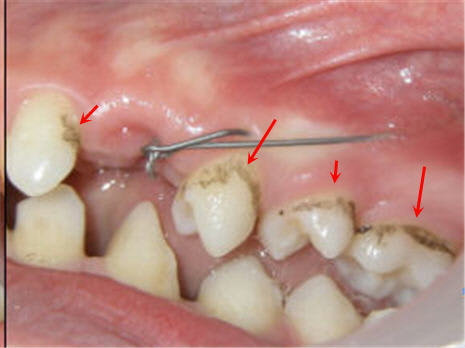

Ben... voici déjà la n°1 :

Sur l'OTP, le déplacement radiculaire de la 12 signe bien la position vestibulaire de 13, mais en bas...

Voici un cliché per-op.

Pour la n° 2, tout le monde est d’accord ?

Daniel